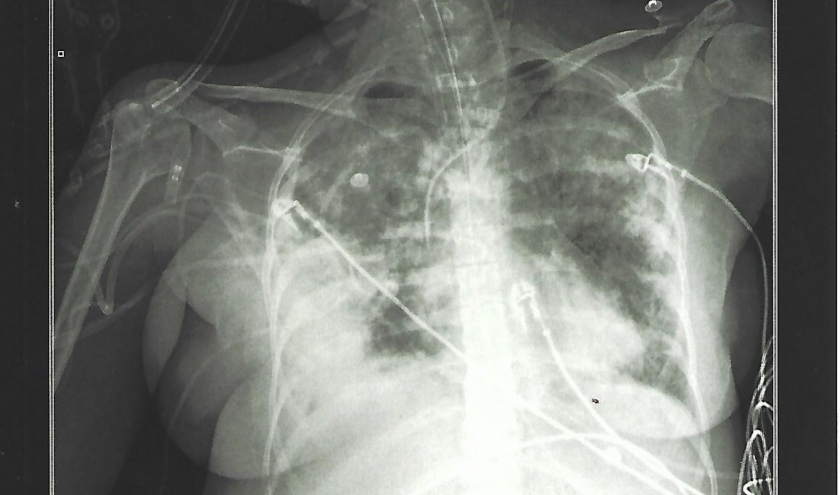

Ce récit est la chronique de dix-sept jours dans une unité de soins intensifs, en 2018, à cause d’un Syndrome de Détresse Respiratoire Aigüe (ARDS), insuffisance respiratoire aiguë secondaire à une inflammation sévère affectant les poumons. Ce même syndrome qui, deux ans plus tard, conduira aux soins intensifs les patients les plus sévèrement atteints par la COVID-19.